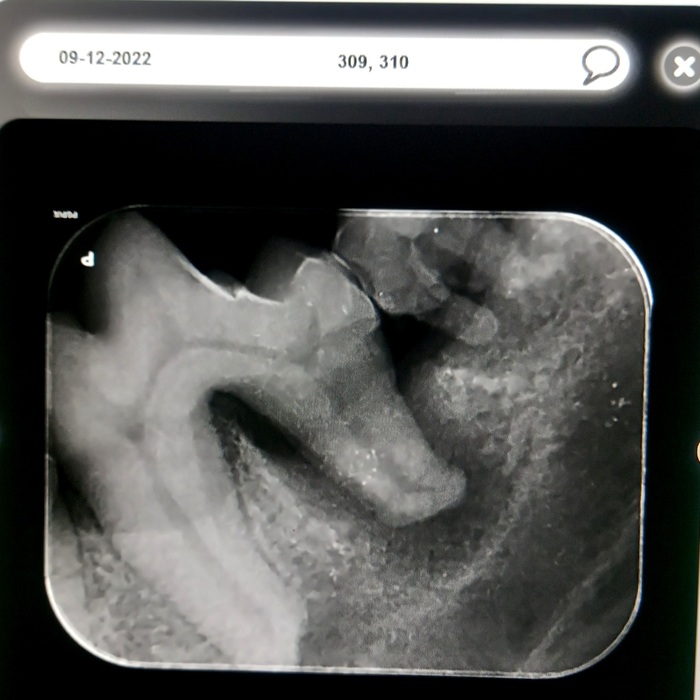

Rentgeny zubů se využívají na zobrazení hlubších vrstev zubů, kořenového systému zubů, posouzení parodontu a čelistních kostní.

Při rentgenologickém vyšetření posuzujeme následující struktury:

Korunka zubu: přítomnost a celistvost skloviny, šířka dentinu a jeho případné patologie, šířka dřeňové dutiny, celistvost zubu, při frakturách rozsah zlomenin, hledáme resorptivní léze, kazy, částečné/úplné fraktury, změny tvaru a celistvosti korunky

Krček zubu: celistvost krčku, resorptivní léze, kazy, fraktury

Kořen zubu: posouzení cementu na povrchu zubů, dentinu, dřeňové dutiny, fraktur kořenů, tvaru kořenů a jeho případných výběžků, přítomnosti tzv. pulpálních kamenů, osteoresorptivních lézí

Čelist: posouzení případných periapikálních reakcí, přítomnosti, úbytku či změny struktury alveolární kosti, přítomnost zlomenin čelisti či nádorového procesu, ne/přítomnost některých zubů

kořenové anomálie

kořeny mléčných zubů

periapikální absces

polámané kořeny v čelisti

vstřebávající se kořen špičáku

resorptivní léze